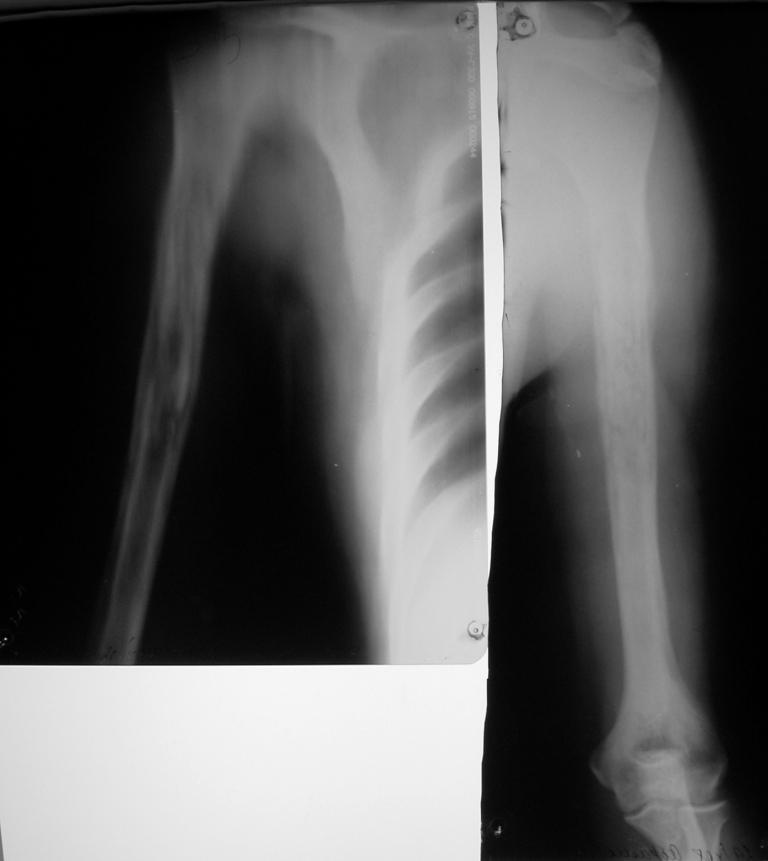

Странно, вчера почему-то не увиделись рентгенснимки. Дифдиагноз с опухолью ИМХО должен быть на первом месте.

Секвестр средней, верхней трети плечевой кости четко виден на снимках - логичным подходом является секвестрэктомия , заполнение полости бусами с гентамицином, аппарат внешней фиксации. Перед началом хиургии сделайте посев свищевого отделяемого, непосредственно перед секвестрэктомией в операционной введите метиленовую синьку в свищевой ход и в процессе доступа к плечевой кости иссекайте прокрашенные ткани. По результату посева начинайте сАБ после хирургической обработки, длительность АБ курса

определяется по показателям СОЭ и С-реакт. белка. После контроля инфекции рассмотреть необходимость костной пластики, если Involucrum недостаточно

разовьётся.

PS *рассверлить* секвестр и удалить его полностью из канала будет сопряжено с потерей неинфицированной кости проксимального идистального отделов плеча, поэтому предлагаю остановиться на открытой секвестрэктомии и иссечении инфицированного мягкотканного футляра.

Несмотря на прежнюю историю с инфицированием необходимо диагноз уточнить. Для доказательства хронического остеомиелита вместо фистулографии можно было бы сделать МРТ.

Она покажет процент вовлечения канала и отдифференцирует хронический процесс от метастаза.

подобная рентгеновская картина гематогенного остеомиелита, острый период которого прошел далеко не в сентябре, а много ранее, леченного активными антибиотиками нуждается в более подробном описании.Это ведь не вопрос-как оперировать, а суть в том, что никогда не знаешь сколько раз еще придется брать этого больного.Хотелось бы более полную информацию о пациенте, включая анализы крови, данные бакпосева, иммунного статуса.Согласен с д-ром Кульджановым о возможности МРТ, если у Вас есть кому эти данные интерпретировать.Необходимость внешней фиксации очевидна.О приготовлении спейсеров и бус с антибиотиками на данном форуме уже не раз писали.